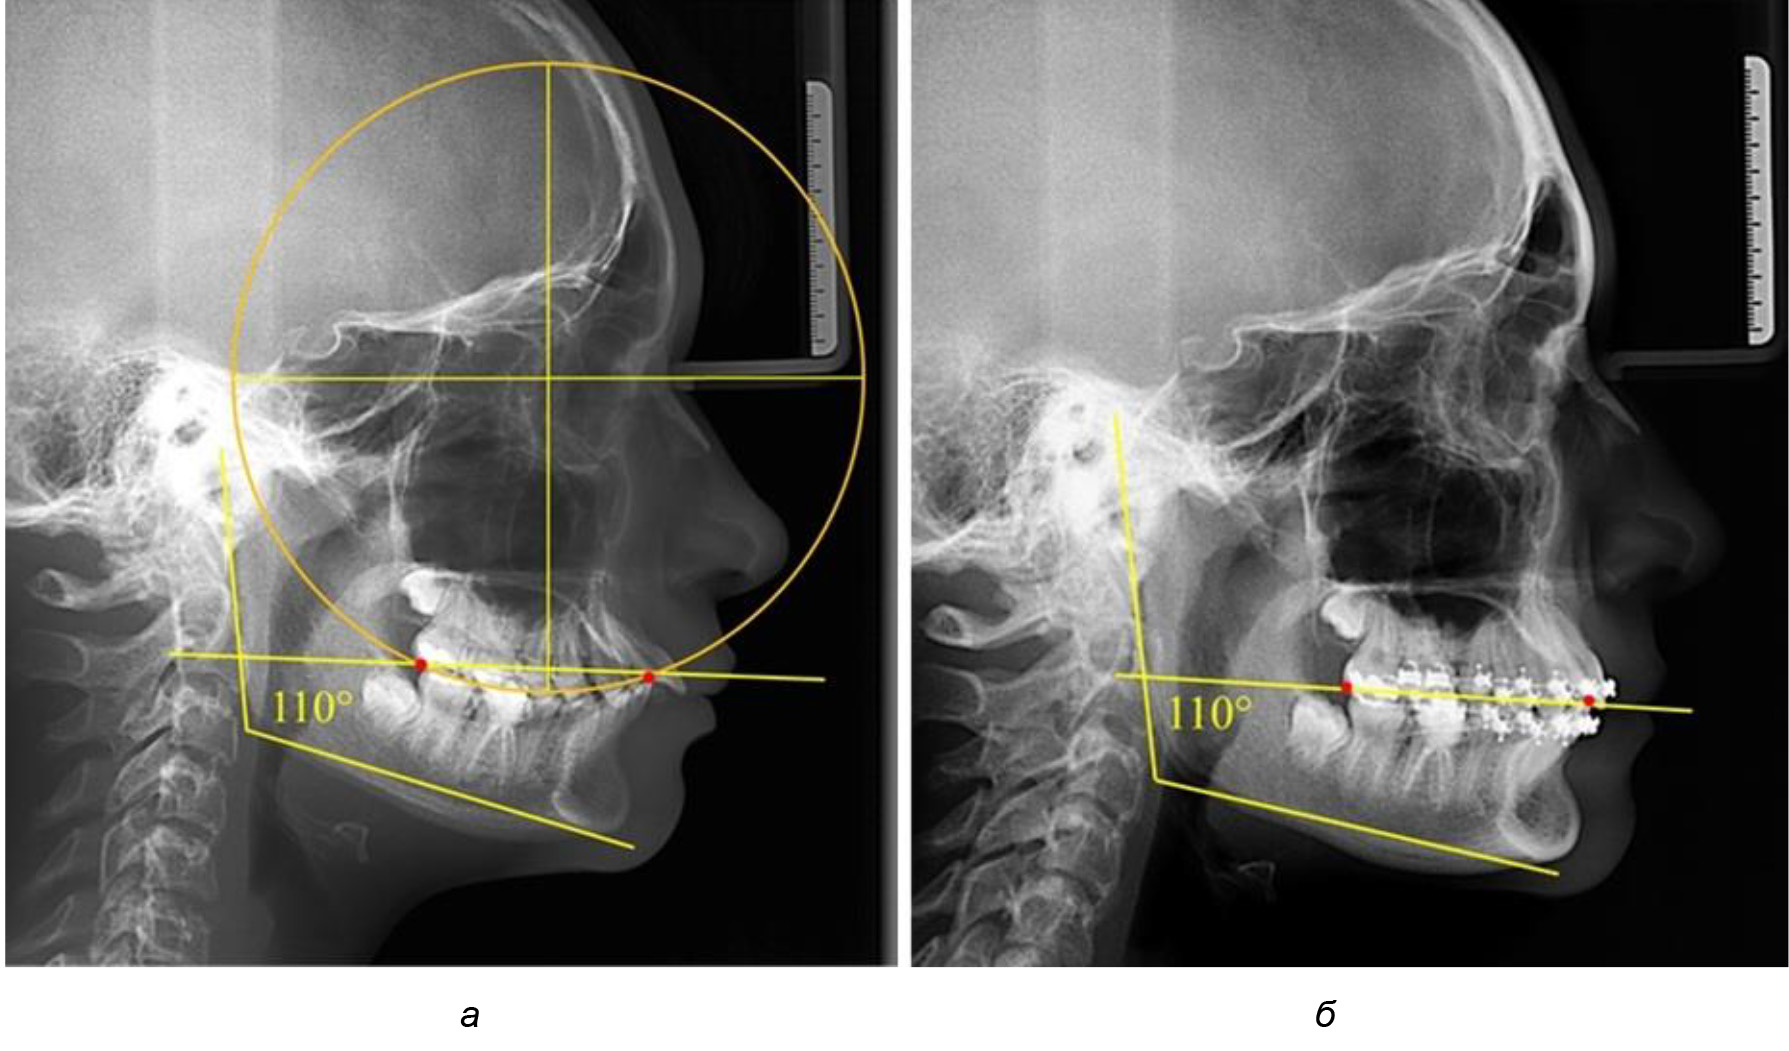

Рис. 1. Метод определения кривой Spee на ТРГ (а) и на ОПТГ (б)

При анализе латеральных ТРГ устанавливали реперный окклюзионные точки в переднем и боковом отделе. Передняя точка устанавливалась на режущем крае нижнего медиального резца, которую в клинике ортодонтии обозначают как vPOcP. Дистальная точка второго нижнего моляра обозначалась как hPOcP. Измеряли расстояние между окклюзионными точками, что определяло сагиттальный размер окклюзионной линии. Использование программ PowerPoint позволило проводить окружность, проходящую по линии смыкания зубов через окклюзионные точки. Измеряли радиус окружности. Учитывая вариабельность размеров окклюзионной линии и радиуса окружности, определяли относительный показатель через отношение радиуса круга к длине сагиттального размера окклюзионной линии. Глубину окклюзионной кривой измеряли от точки наибольшей выпуклости до окклюзионной линии (рис. 1). На ортопантомограмме (ОПТГ) также соединяли окклюзионные точки правой и левой стороны и измеряли глубину окклюзионной кривой от точки наибольшей выпуклости до окклюзионной прямой линии. Результаты глубины кривой Spee сравнивали по данным ТРГ и ОПТГ.

Деление величины радиуса круга к длине окклюзионной линии составило 1,623 ± 0,02. Таким образом, для определения радиуса окружности, соответствующей кривизне окклюзионного контура боковой ТРГ, необходимо измерить расстояние между передней и задней окклюзионными точками и последующим умножением полученной величины на число Фибоначчи (рис. 2).

Рис. 2. Особенности кривой Spee на ТРГ (а) и ОПТГ (б) у людей с признаками вертикального роста